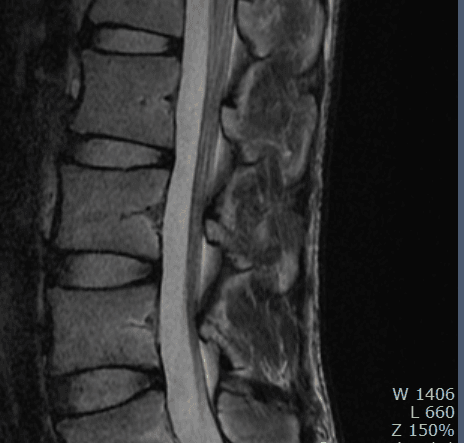

이런 경우에 골절이 아닌지 오해하시는 경우가 많은데 골절이 아닙니다.

골절의 경우에는 T1 영상에서 조영이 떨어지고 fat suppression T2 영상에서 조영이 증가하는 소견을 확인해야합니다.

골절이 아니면 왜 저렇게 보이는지 까지는 제가 잘 모르지만 저 소견을 이상소견으로 보이는 않습니다.